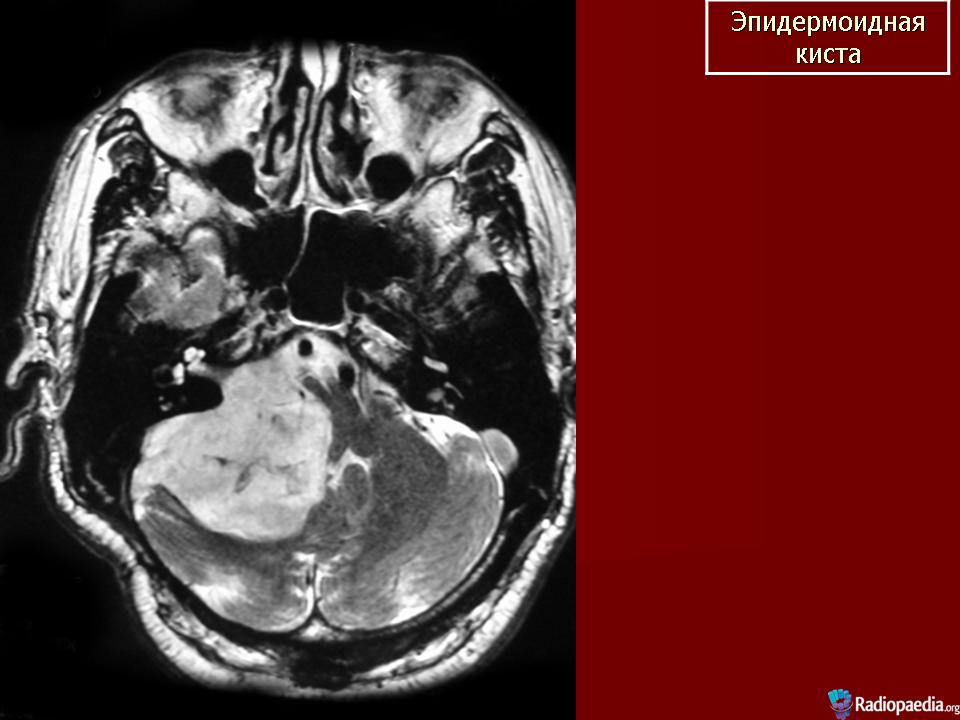

Эпидермоидная киста

ID: 5664 Epidermoid cyst (small pre-pontine) Dr Frank Gaillard - 5 Mar 2009 MRI demonstrates a small region in the pre-pontine cistern with distorti...

ID: 9772 Epidermoid cyst - cerebellopontine angle Dr Frank Gaillard - 23 May 2010 Characteristic appearance of an epidermoid cyst in the cerebellopon...

ID: 2609 Epidermoid cyst - cerebellopontine angle Dr Frank Gaillard - 7 May 2008 This patient had a right sided cerebellopontine angle mass (shown to be ...

ID: 4366 Epidermoid cyst - cerebellopontine angle Dr Frank Gaillard - 14 Aug 2008 Selected images from an MRI demonstrating both typical appearances and l...

ID: 13721 Epidermoid cyst - cerebellopontine angle Royal Melbourne Hospital - 10 May 2011 This case demonstrates typical appearances of a large cerebellopontine a...

ID: 15137 Epidermoid cyst - cerebellopontine angle Dr Frank Gaillard - 25 Sep 2011 This case demonstrates typical location and appearances of an epidermoid...